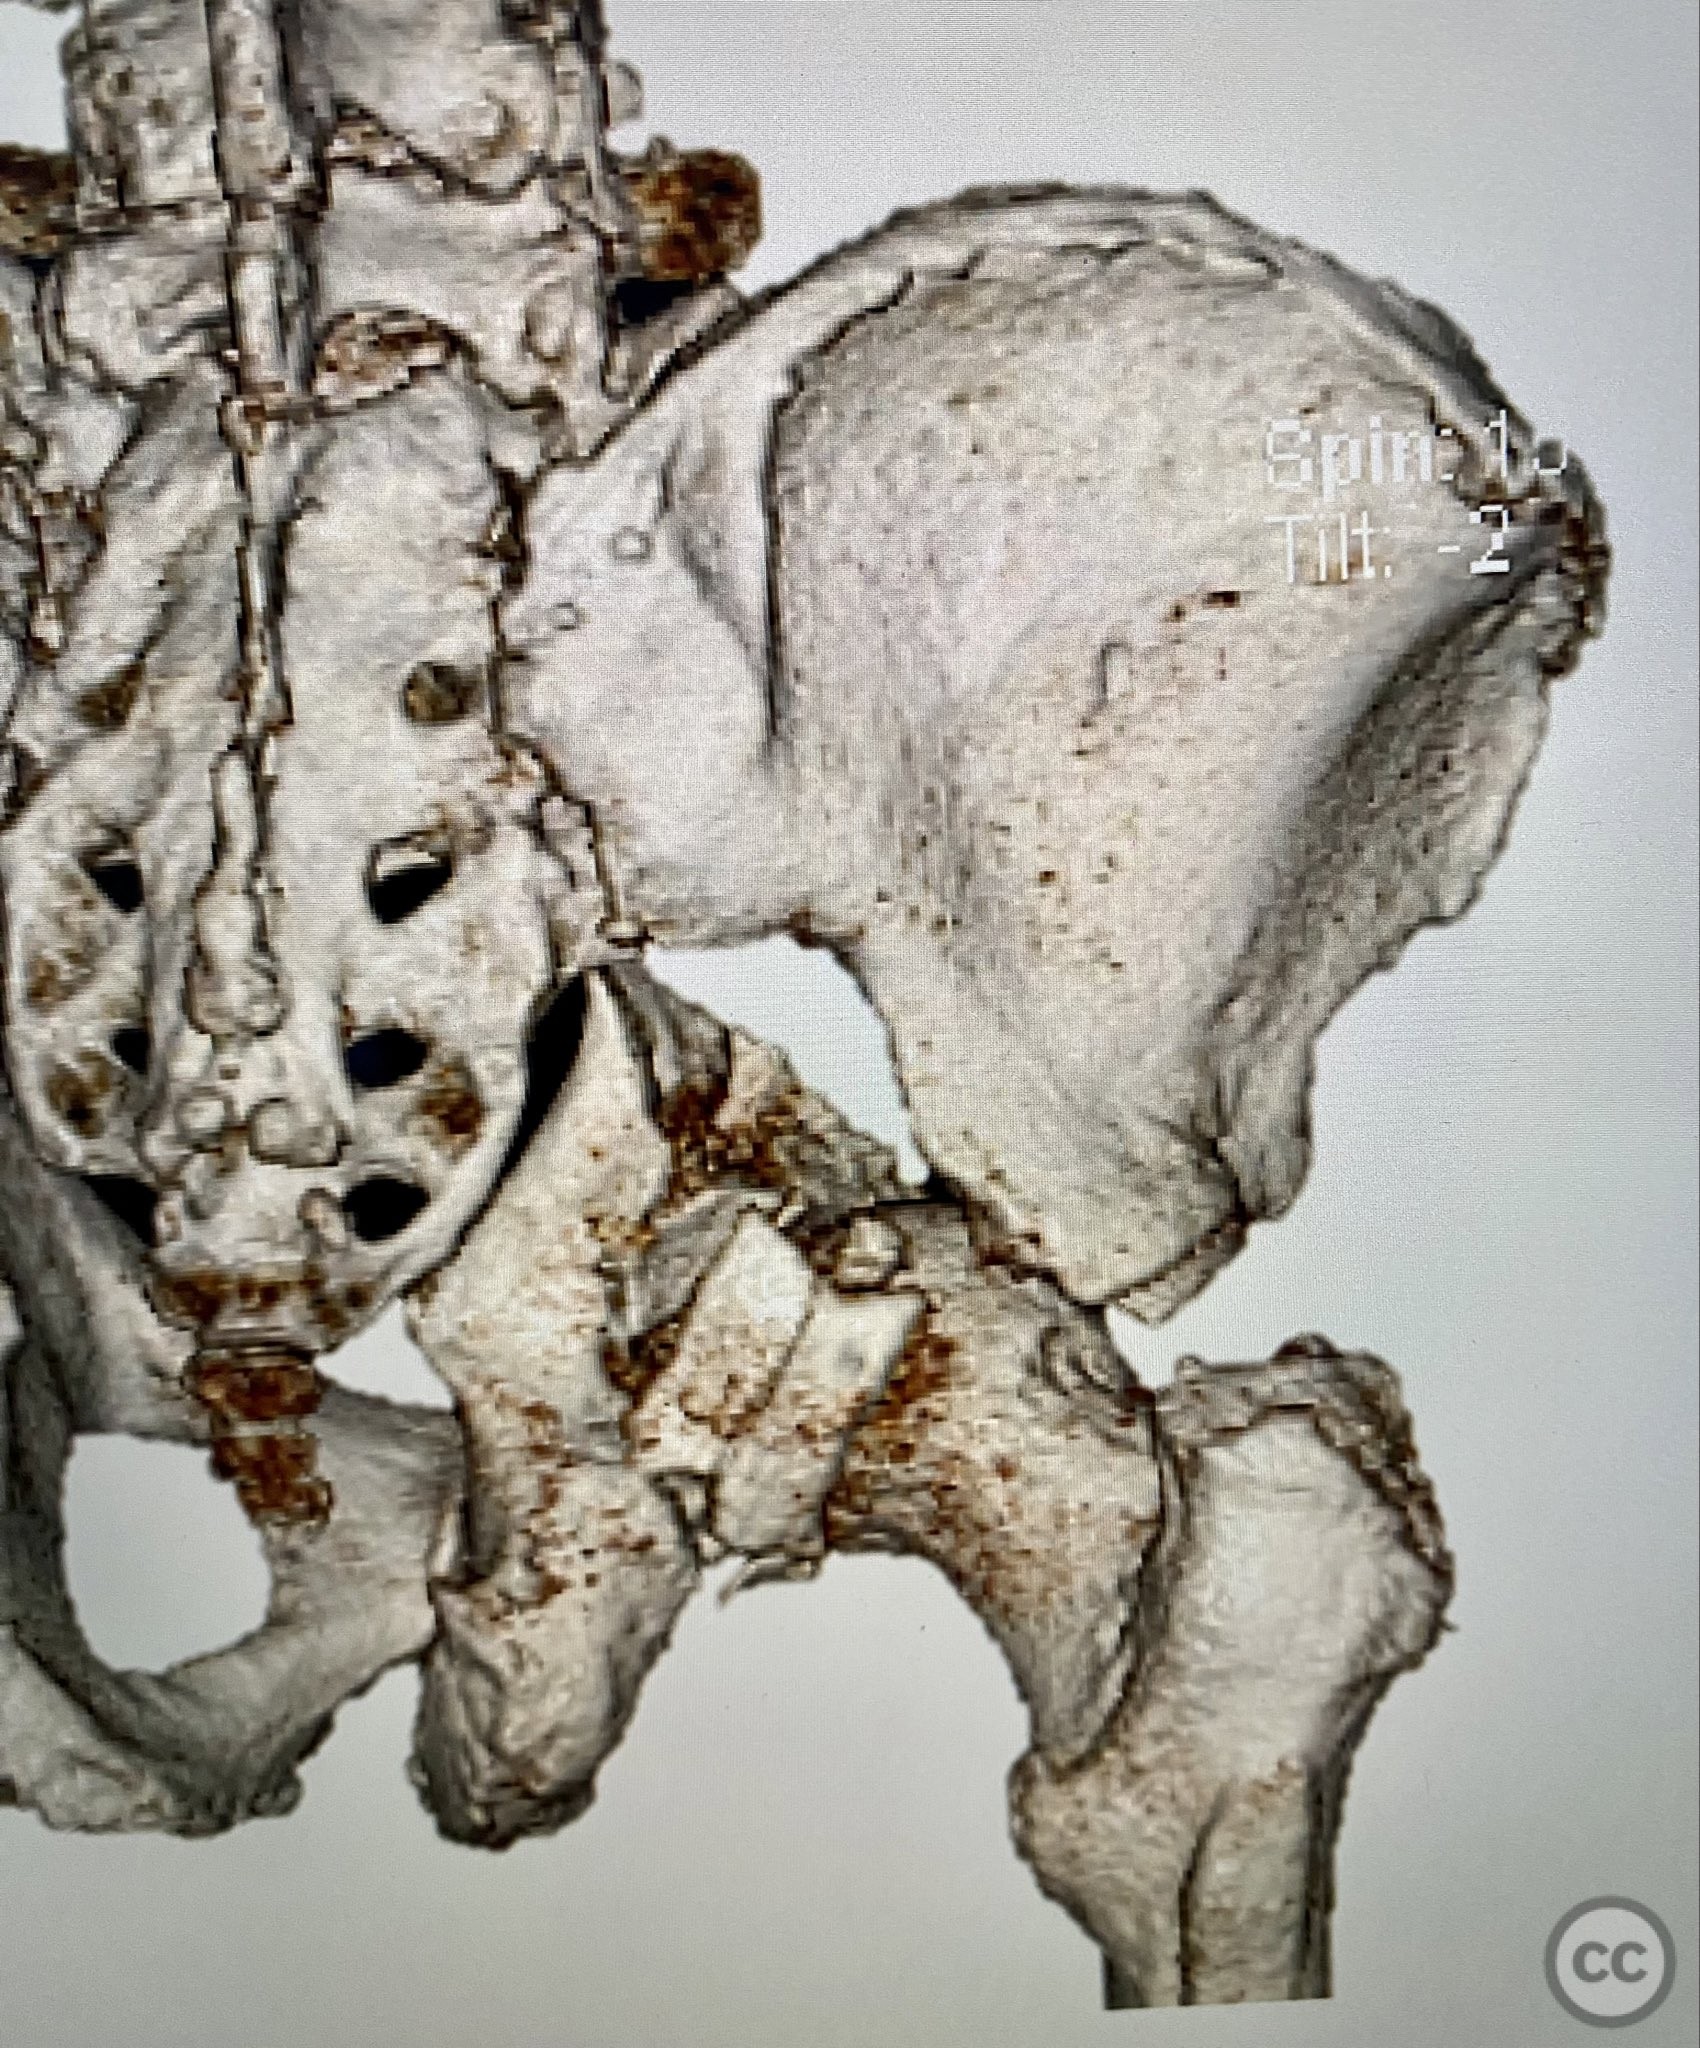

Clinical and radiological findings:  A 79-year-old male sustained a high-energy injury in a motor vehicle collision, resulting in a complex acetabular fracture-dislocation. Radiographs and computed tomography demonstrated a posterior wall and transverse acetabular fracture (AO/OTA 62-B1.3), with the posterior wall fragments displaying an atypical caudal hinge configuration. The medial wall fragment was non-articular. Axial imaging revealed an impacted osteochondral fragment obstructing reduction, as well as disruption of the capsular structures adjacent to the intact articular segment. The obturator internus tendon appeared taut but intact, with no evidence of sciatic nerve impingement or superior gluteal neurovascular compromise.

Anatomical surgical approach:  A standard Kocher-Langenbeck approach was performed, incising through the gluteal fascia and splitting the fibers of the gluteus maximus. The short external rotators were identified and protected, with subperiosteal dissection exposing the posterior column and wall of the acetabulum. The sciatic nerve was identified and mobilized laterally. The posterior capsule was found disrupted adjacent to the intact articular surface. The impacted osteochondral fragment was extracted from the joint space. The transverse fracture plane was debrided and reduced using clamps, with a greater trochanteric bone hook employed to manipulate the femoral head beneath the acetabular dome during reduction. Provisional fixation was achieved with a percutaneous lag screw across the transverse component. The peripheral posterior wall fragment was anatomically reduced and stabilized with a contoured plate. The medial wall defect provided access for reduction of the impacted articular segment, which was bone grafted prior to reduction and plating of the medial wall. Capsular tissues were repaired with nonabsorbable sutures prior to layered wound closure.

The posterior wall fragments exhibited an unusual caudal hinge morphology, necessitating careful mobilization to avoid propagation or comminution. Removal of the impacted intra-articular fragment was essential to achieve concentric reduction of the femoral head within the acetabular dome. Use of a greater trochanteric bone hook facilitated precise control of femoral head position during reduction maneuvers. The medial wall fragment, though non-articular, allowed direct visualization and accurate reduction of the impacted osteochondral segment, which was supported with bone graft prior to definitive fixation. Repair of disrupted capsular tissues was performed to restore soft tissue integrity and potentially reduce postoperative instability.